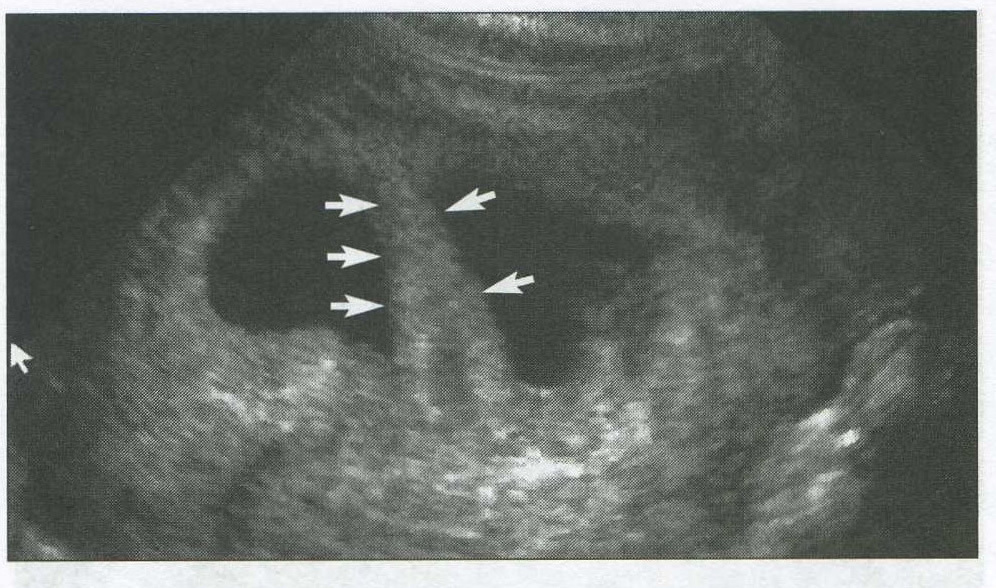

identify the structure that the arrows are pointing to in this 6 week gestation

decidua capsularis